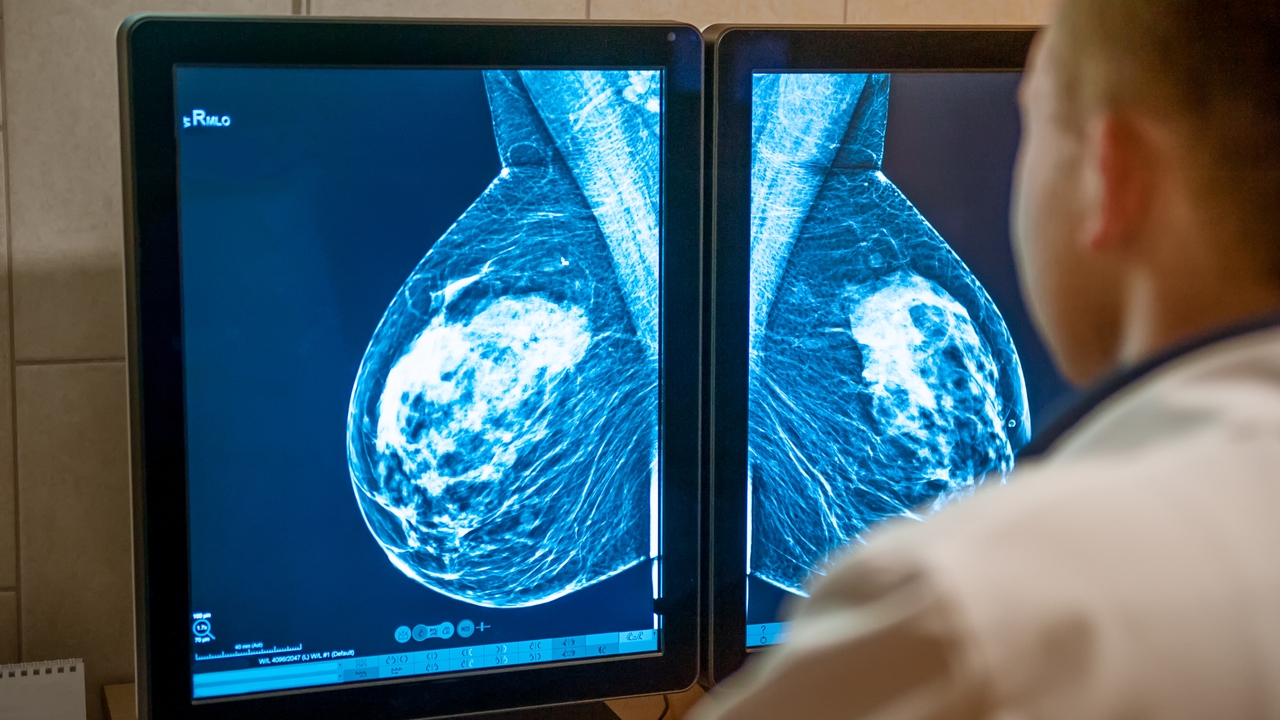

Quimioterapia en desescalada: una realidad de cada vez más pacientes con cáncer de mama

A los biomarcadores y pruebas genéticas, como la determinación de DNA circular tumoral, se suman terapias farmacológicas que hacen que el uso de la quimio en muchos casos sea innecesario...